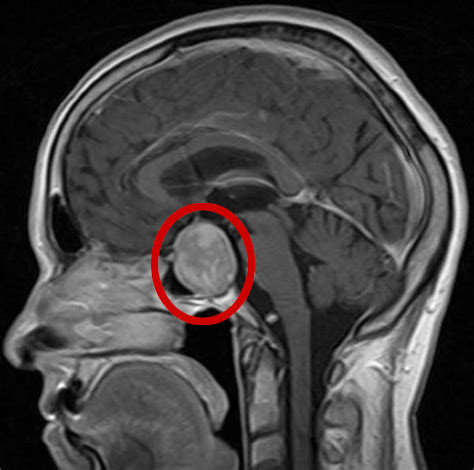

Adenoma ipofisario

- Descrizione: Tipo di Tumore benigno che nasce nella ghiandola Ipofisi, nell'area della adenoipofisi.